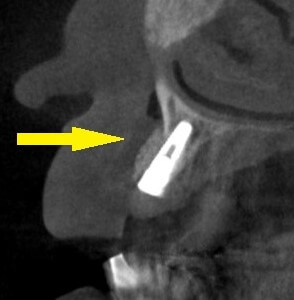

3段目の写真が手術後のCTです。

インプラントの外側に、骨補填材が白く写っています。